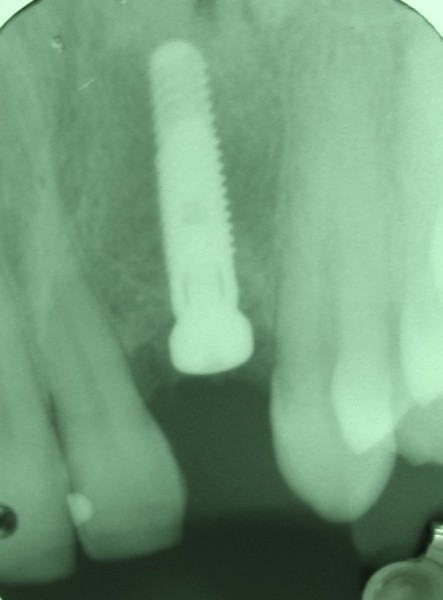

Sinus Lift With Simultaneous Implant